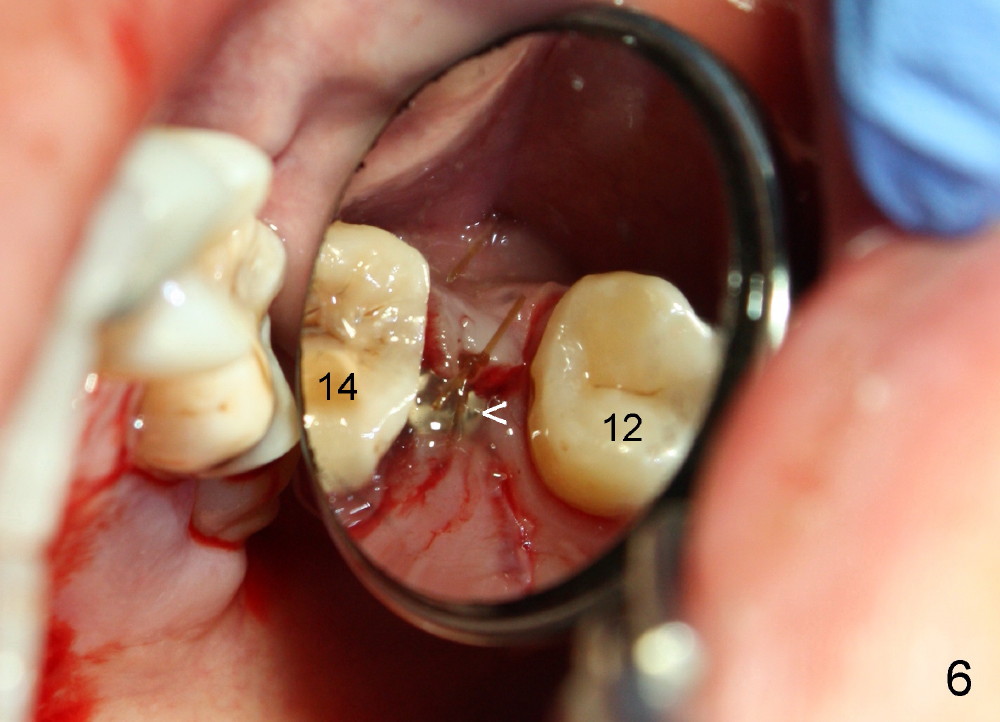

A 39-year-old lady is a dental phobic and finally agrees to restore long-termed missing upper left 2nd premolar (Fig.1). The adjoining teeth tilt toward the edentulous space. To place a 3.8x8 mm submerged implant (Fig.2, CBCT coronal section), enameloplasty is done (compare Fig.1 dashed lines with Fig.3 <). Since the density of the cancellous bone (<100 Hounsfield units (HU)) is much lower than that of the crest (300-400 HU) (Fig.2' <), osteotomy is initiated by 2 mm pilot drill (Fig.3 P) and finished by osteotomes (2 and 3 mm), bone expanders (2.6 mm (Fig.4) and 3.2 mm) and 3.8 mm tap drill. The implant is placed as planned with insertion torque around 35 Ncm (Fig.5). The implant is further lifted into the sinus by 1 mm without bone graft following the last X-ray. A healing abutment (4.1x3) is placed (Fig.6 <).

Limited orthodontic treatment is planned to close the diastema between the canine and the first premolar (Fig.1 ^) and to upright the molars, probably using osteointegrated implant as an anchorage.